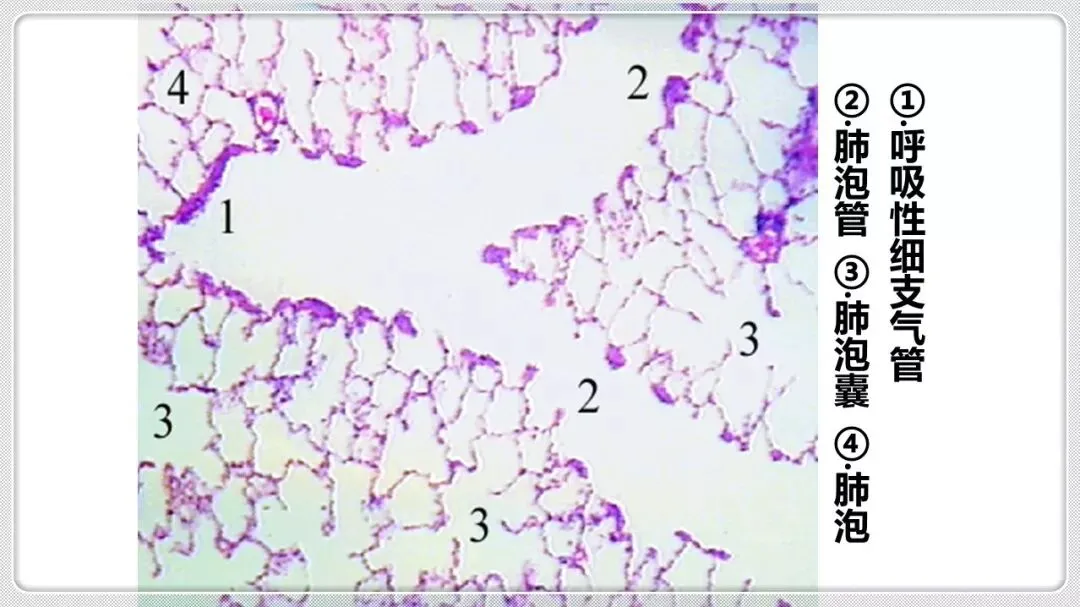

组织学与胚胎学笔记pdf【 常考图谱】

组织学与胚胎学 图谱